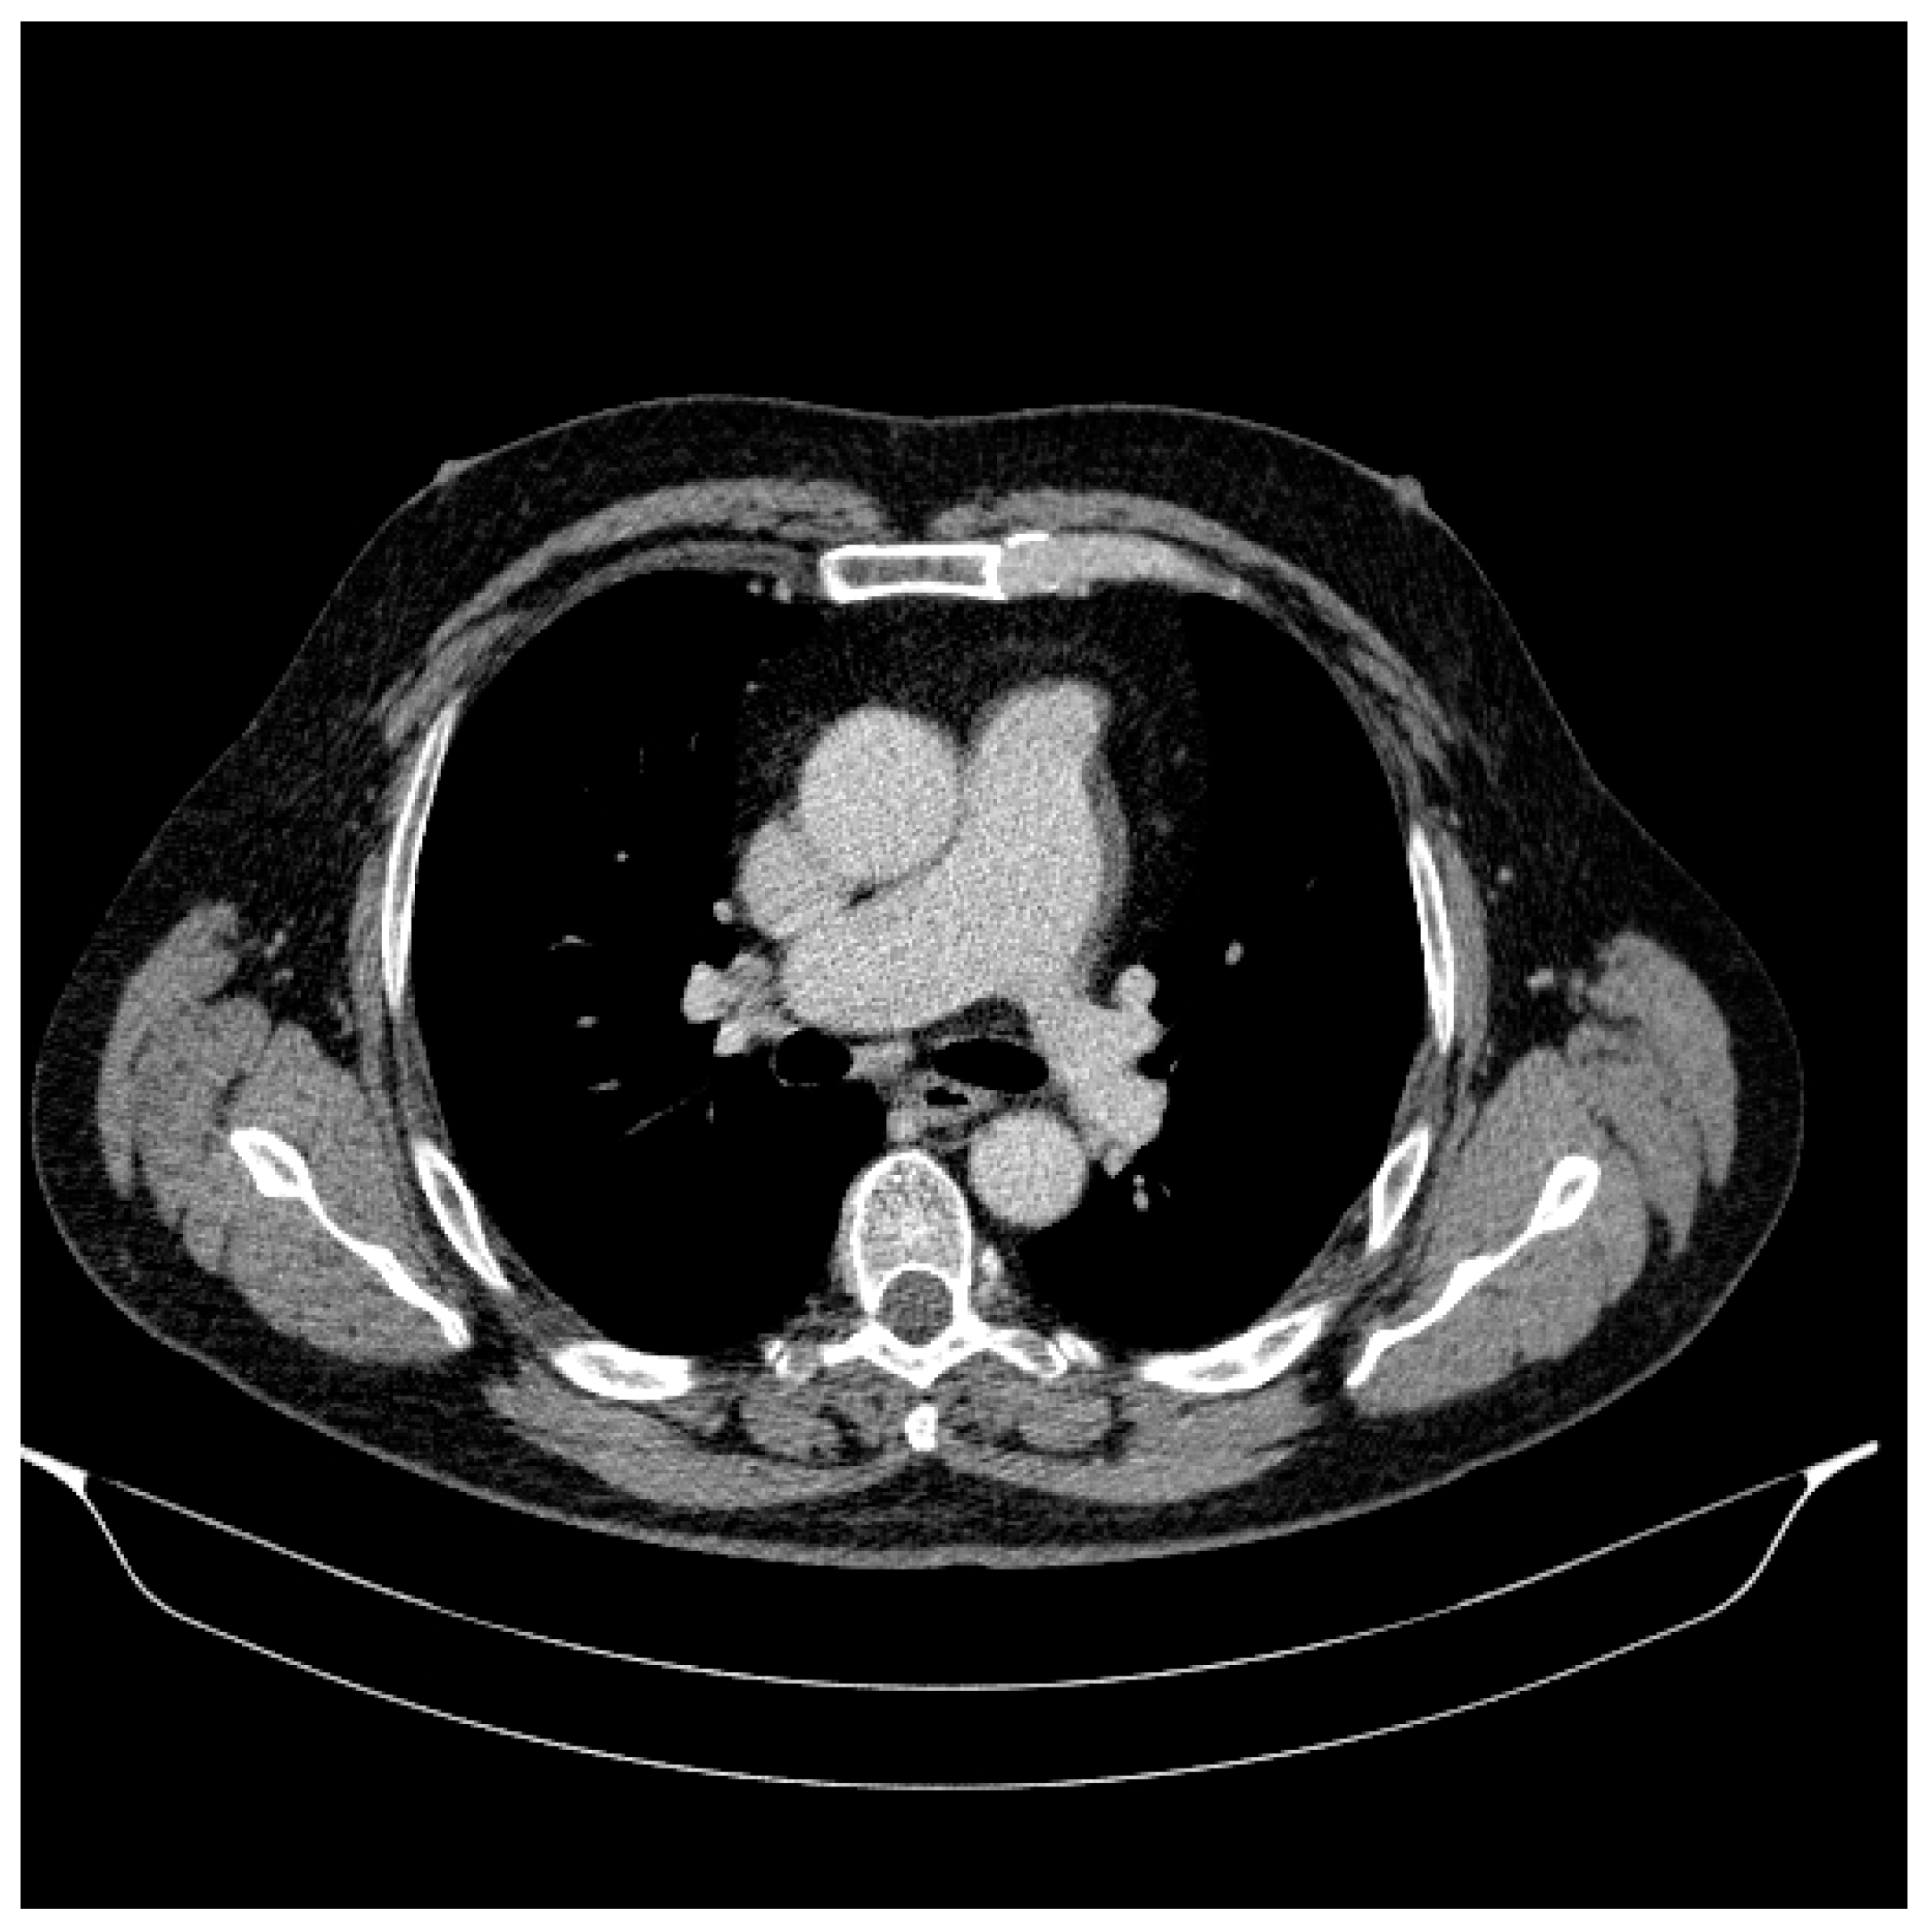

2.2. At the Thoracic Level